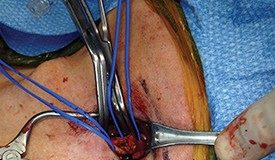

Changing the game in knee osteoarthritis: A vascular approach

Chinmaya Shelgikar, MD, discusses the benefits of vascular surgeons performing geniculate artery embolization.

Geniculate artery embolization (GAE) is an intra-arterial, catheter-based procedure used to treat chronic...